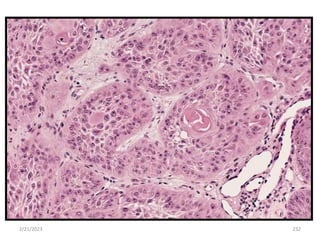

2/21/2023 232

2/21/2023 233